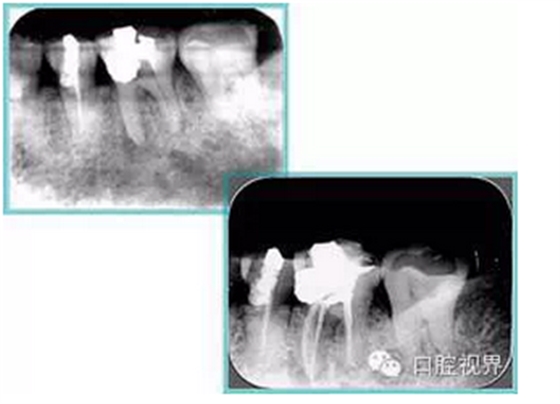

共有 4 張 X 線片,分別是術(shù)前、診斷絲 、主牙膠尖確認、術(shù)后。

( 1 )術(shù)前:術(shù)前 X 線片用來了解牙齒的大概情況。術(shù)前預(yù)期為多根牙時 X 線片應(yīng)偏頭拍攝。

( 2 )診斷絲:根據(jù)術(shù)前 X 線片進行開髓、根管的初步預(yù)備后,需要插入診斷絲,用來指示工作器械位置。常用 10 號或 15 號擴大器作為診斷絲插入牙髓腔。

( 3 )主牙膠尖確認:通過術(shù)前預(yù)期和診斷絲診斷,明確工作長度、牙根走向,進行根管預(yù)備。之后應(yīng)進行主牙膠尖(中銼)確認,已明確根管是否適合充填。

( 4 )術(shù)后:觀察治療效果。

左圖為根管充填術(shù)后 X 線片。圖中可見,根管充填較好。右下圖有白色小點,為側(cè)方加壓導致糊劑擠出所致,表明根管充填比較致密。

多根牙時候需進行偏移投照,正位投照無法說明具體哪根牙根管充填效果。